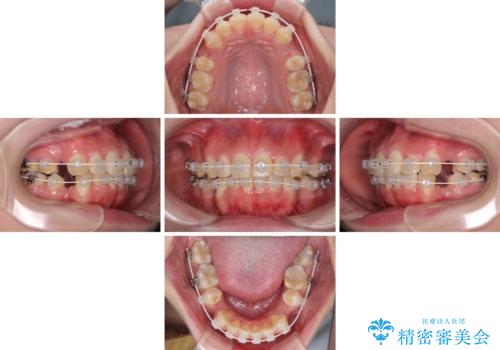

- 矯正装置

- 審美装置

- 治療期間

- 1年10ヶ月